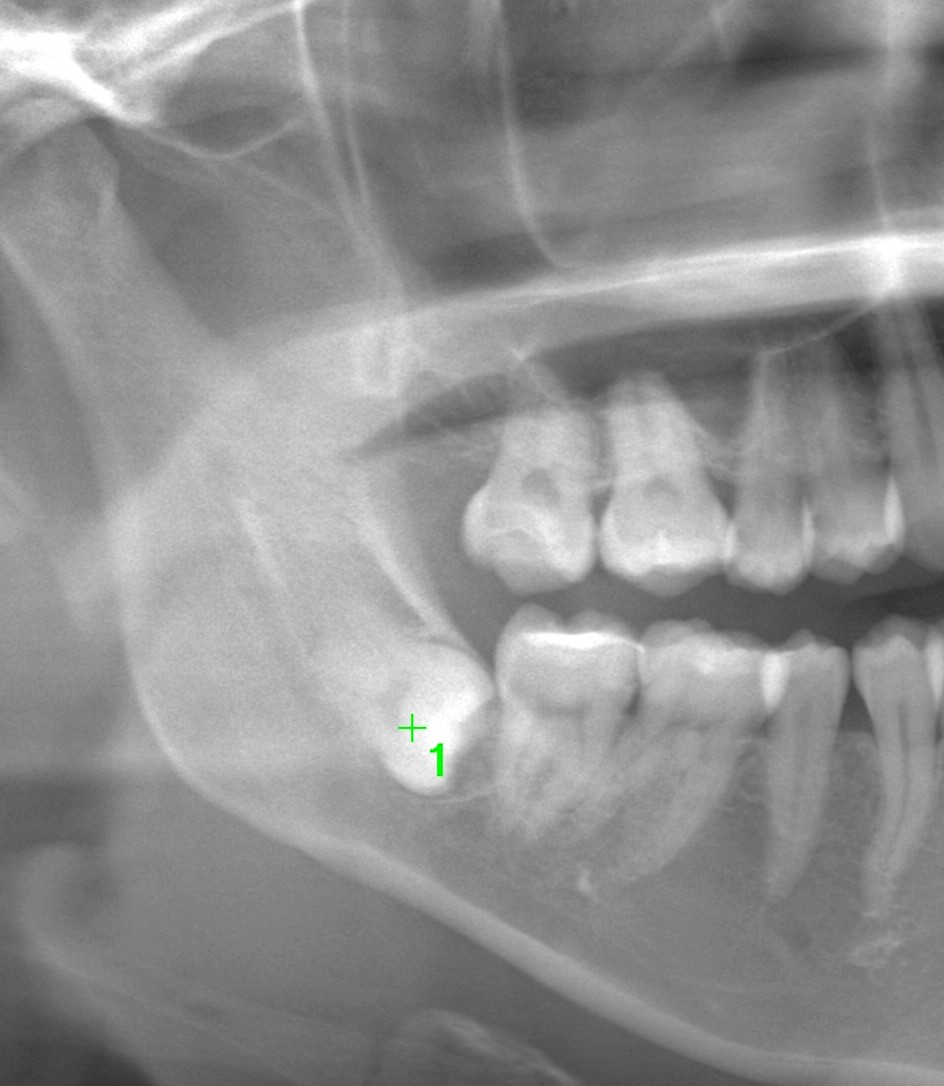

まずはパノラマ(2Dレントゲン)で確認

撮影してみると、右下の親知らずは骨の中に深く埋伏していました。

埋伏の向きは下方(深部)へ向いており、神経との距離も近そうです。

このタイプは、抜歯の際に神経へ影響が出るリスク(術後のしびれ)が相対的に高く、難易度も上がります。

以前に経過観察となった理由も、まさにこの点だったと推測されます。